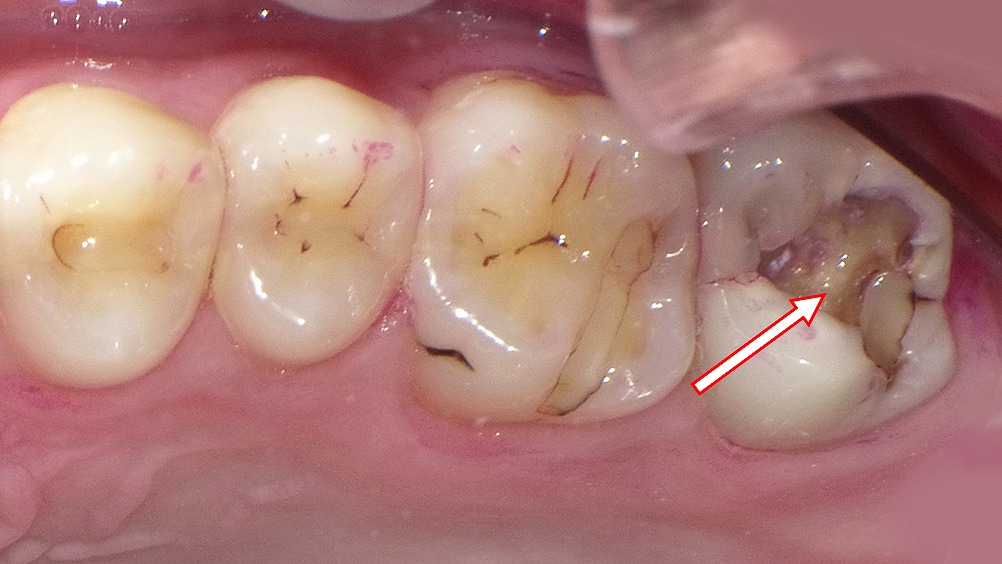

この写真は上顎第2大臼歯(7番)を中心に撮影された画像です。赤い矢印で示されている部位に、う蝕(虫歯)の進行が確認されます。以下に詳しく解説します。

🦷 状況の概要

矢印部の**上顎右側第2大臼歯(7番)には、咬合面から近心側(手前方向)にかけて大きく崩壊した虫歯(C3)**が認められます。

象牙質の深部まで進行し、一部では歯髄(神経)に近接していることがうかがえます。

🩺 臨床所見

- 歯種:上顎右側第2大臼歯(7番)

- う蝕分類:C3(歯髄に近い象牙質う蝕)

- 症状:

- 冷たいもの・熱いものにしみる(温度刺激痛)

- 自発痛なし(持続的なズキズキはない)

- 歯髄反応:可逆性歯髄炎の可能性

- 歯質:咬合面~隣接面にかけて軟化象牙質あり

- 周囲歯肉:軽度の炎症あり、腫脹や排膿は認められない

🧬 診断

- 診断名:C3(象牙質深部う蝕・歯髄刺激あり)

- 歯髄の状態:生活歯、歯髄炎が進行中の可能性(可逆性~初期不可逆性の境界)

💡 治療方針(例)

- う蝕除去と歯髄の状態確認

→ 露髄(神経が出る)可能性あり。 - 歯髄保存療法または根管治療の判断

- 反応が軽度であればMTAセメント等による覆髄処置

- 痛みや感染が進行している場合は根管治療(神経の除去) - 最終修復

- コンポジットレジンやセラミックインレー/クラウンで形態回復 - 再発予防

- 咬合面の清掃指導(特にフロス・歯間ブラシの活用)

⚠️ 放置した場合のリスク

この段階で治療を行わないと、虫歯が歯髄まで達して強い自発痛(夜間痛)や腫れが生じ、根管治療が必須になります。

現在のように「冷たい・熱いものでしみる」段階での早期介入が、歯を残す最良のタイミングです。